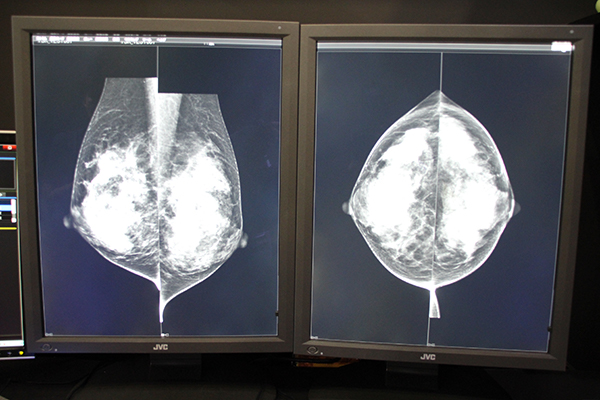

ネットカムシステムズは,ブースの中央に社章にも使用されているピンクリボンをライトアップし,乳腺画像診断ワークステーション「mammodite」の実機を使って,担当者から説明を受けながら体験できる展示を行った。ブースでは読影室の環境に近い,光の反射などを極力抑えられた個室が設けられており,JVCケンウッド,EIZO,バルコなど各社の最新モニタでmammoditeのパフォーマンスを落ち着いて体験できるようになっていた。

各個室では各メーカーの最新モニタによるmammoditeが展示されている。

ビューワは独自開発の統合プロセスエンジン「APROS」により,トモシンセシスも含めたマンモグラフィ画像も待ち時間なしに画像表示できるため,ストレスなく読影できる。また,ユーザーインターフェイスはシンプルで直感的な操作性を実現し,各種検査画像の比較の際に読影レイアウトをクリック1つで切り替えられる“ワンタッチレイアウト”機能などを搭載している。ワンタッチレイアウトは,過去画像との比較はもちろん,2Dやトモシンセシスの比較,または乳腺エコーとの併読など,画面レイアウトの表示アイコンをクリックするだけなので,プロトコールの順番や特殊な設定が入っているなどの読影ミスにつながることがない。

mammoditeのビューワ。待ち時間なしに表示することができる。